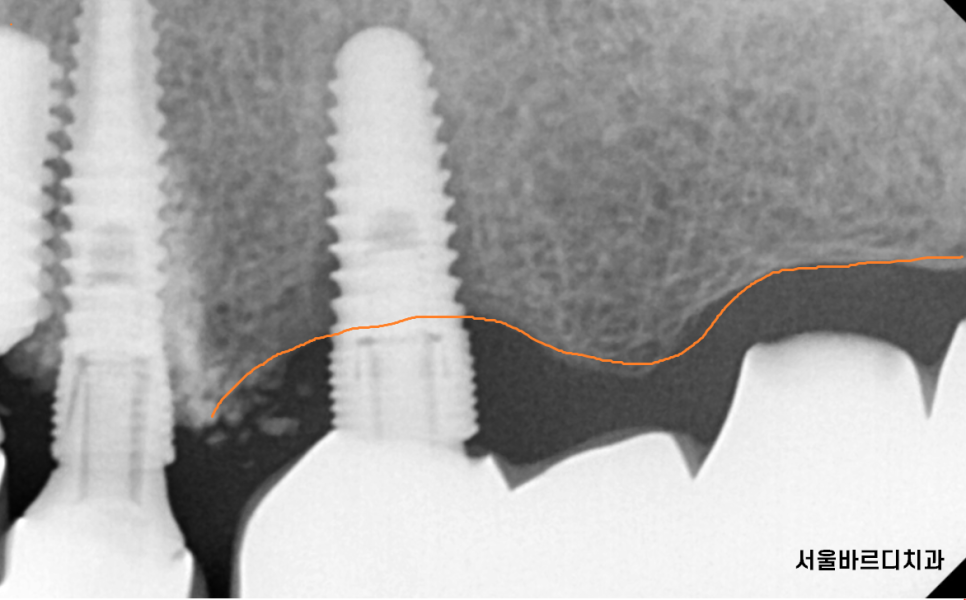

23.06.20

임플란트가 이가 빠지듯

쏘옥 빠지게 됩니다.